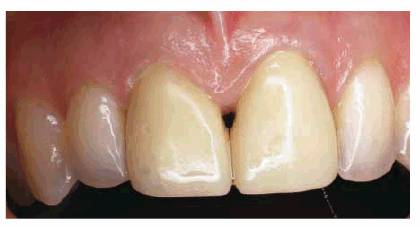

esthetics (Figures 23-13A, 23-13B and C).

Figure 23-13A: When a diastema of this size is to be closed using composite resin bonding, a hybrid material should be chosen on the lingual surface for strength.

Figure 23-13B and C: To obtain a maximum "glaze" or polish to match existing enamel, a microfilled composite resin can be used on the labial surface. Note the glazed appearance of the labial microfilled polished composite resin.